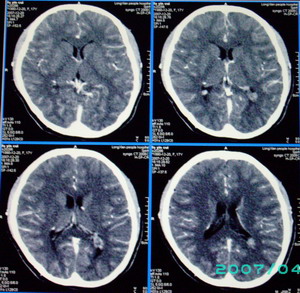

以下是引用九目段在2007-12-24 14:55:00的发言:[br]1,年轻女性[br]2,ct表现:左侧脑室三角区可见一不规则小明显强化的结节,中央见小低密度,侧脑室无扩张。[br]分析:[br]常见的有三种肿瘤好发三角区:[br]1,脉络丛乳头状瘤,好发于年轻者,明显强化,实性,分泌脑脊液,常伴有侧脑室扩大,肿瘤较小可以脑室扩大不明显,不能排除,但小结节尚不易形成坏死腔。[br]2,室管膜瘤,好发于儿童及青少年,明显强化,易坏死,大时伴脑室扩张。[br]3,脑膜瘤,明显强化,圆形,界请,无脑积水,一般不坏死。[br]诊断:[br]左侧脑室三角区结节,考虑室管膜瘤可能性大,不排除脉络丛乳头状瘤和脑膜瘤(因病史较长)。[br][br][本贴已被 九目段 于 2007-12-24 15:13:35 修改过]